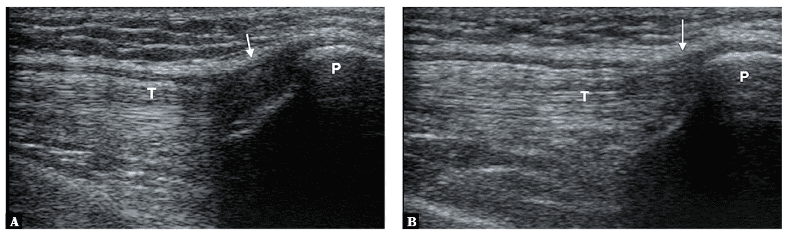

Figure 3. Anisotropy artifact in the image on the left (A) seen in the region of insertion of the quadriceps femoris tendon (T). Image on the left (B) shows reduced anisotropy artifact simply by adjusting the angulation of the transducer footprint relative to the quadriceps femoris tendon and slight flexion at the knee. Image courtesy of Małgorzata Serafin-Król et al. See reference article in the references section.